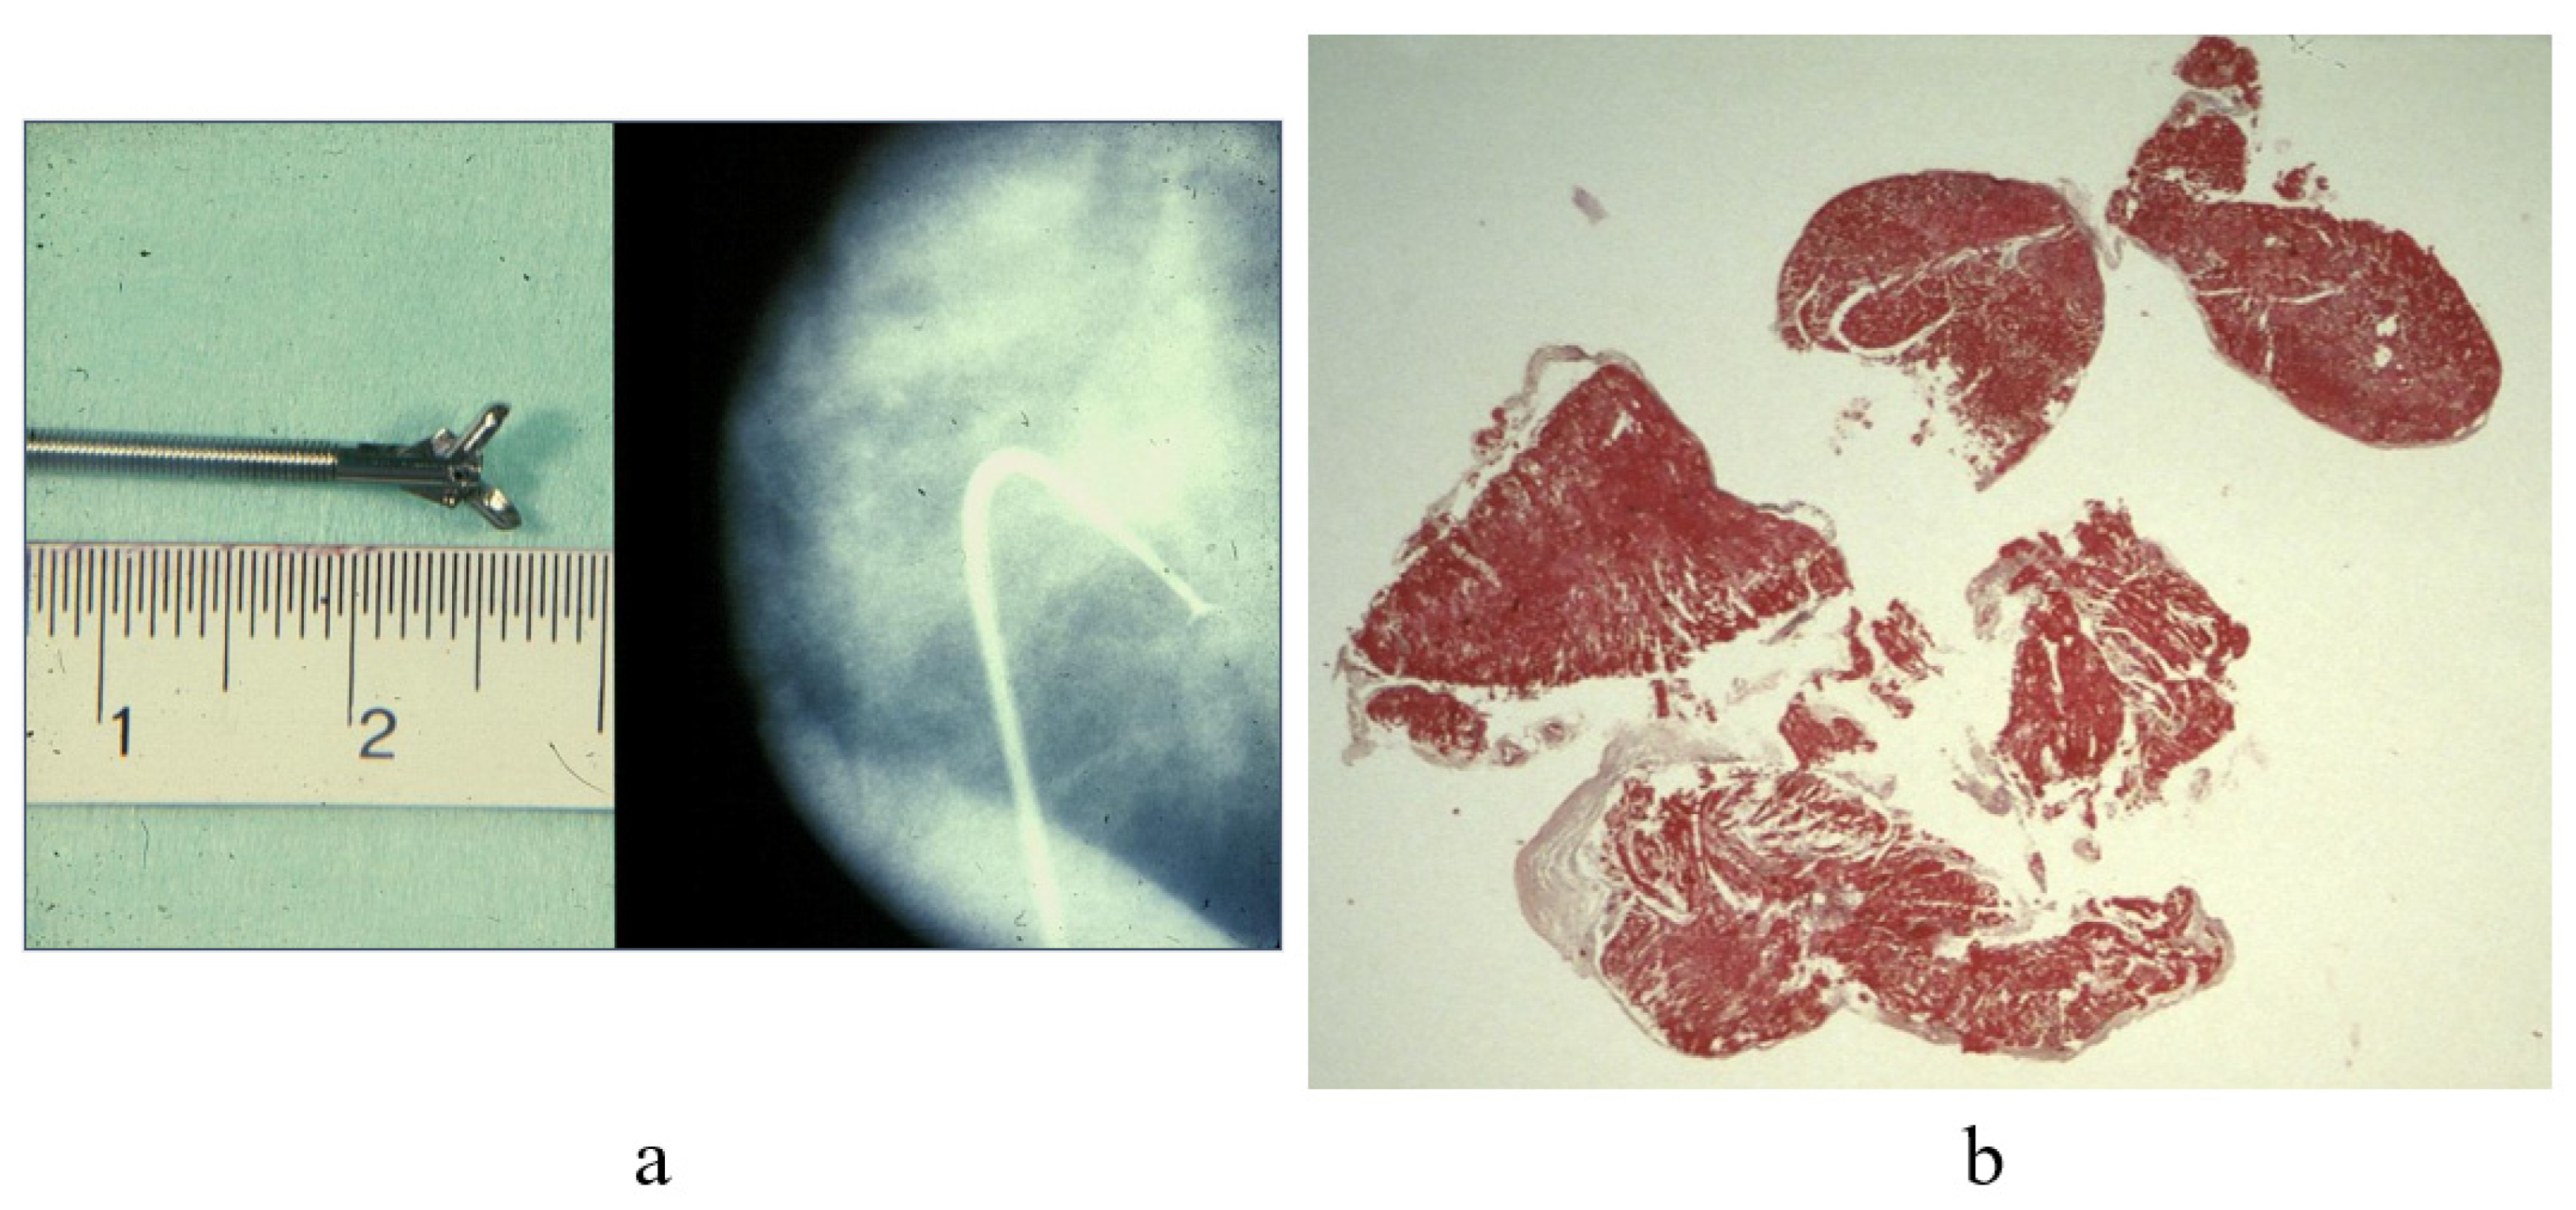

1. Introduction: History of Cardiac Biopsy

7. Clinical Indications of Endomyocardial Biopsy